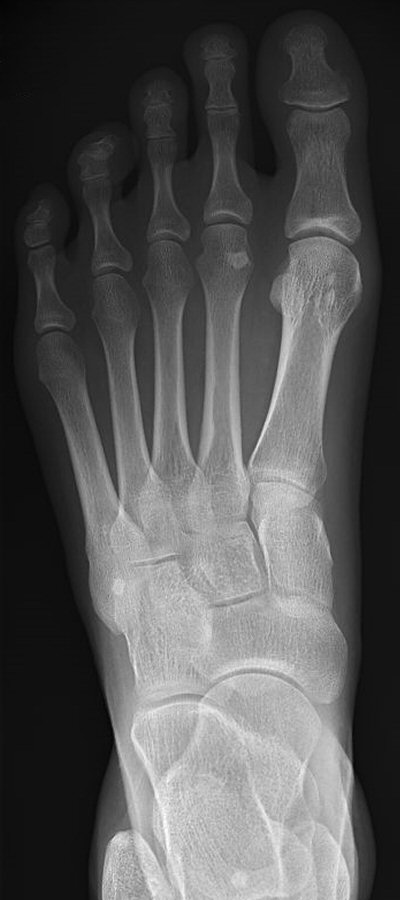

Fraktur på mediala sesambenet, första två bilderna efter en månad, tredje bilden efter 5 månader